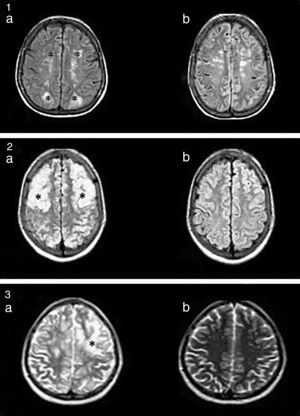

La resonancia magnética nuclear (RMN) (fig. 1) es el método de mayor valor diagnóstico, y permite diferenciar este síndrome de lesiones isquémicas agudas4.

1.a. Lesiones hiperintensas en FLAIR, córtico-subcorticales, simétricas, parieto-occipitales (*). b. Evidencia de mejoría luego de 3 meses. 2.a. Imágenes hiperintensas en FLAIR, bien definidas, bilaterales, que comprometen regiones córtico-subcorticales, fronto-parieto-temporo-occipitales bilaterales (*). b. Evidencia de mejoría a los 2 meses. 3. Lesión hiperintensa en T2 (*). No se evidencian alteraciones en la secuencia de difusión.